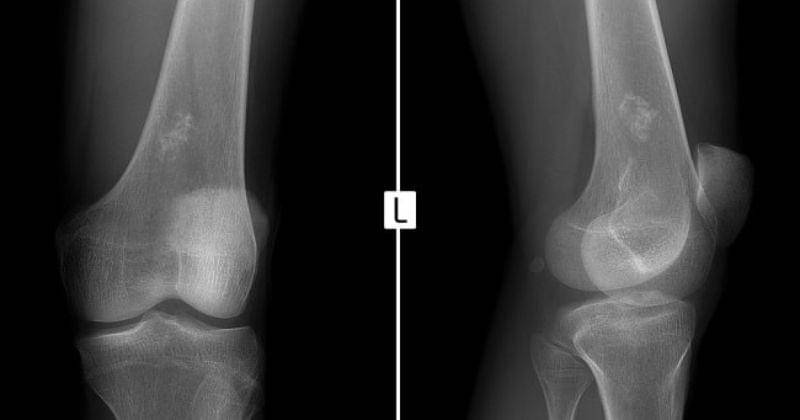

Kelainan yang terdapat pada tulang juga merupakan salah satu faktor utama yang dapat menyebabkan terjadinya kanker tulang pada anak. Beberapa anak yang memiliki kelainan tulang seperti paget sangat berisiko terkena kanker tulang.

Paget merupakan kelainan tulang yang bersifat kronis dan mempengaruhi pembentukan dan pemecahan tulang. Pada kasus ini, tulang baru tumbuh secara abnormal dan lebih cepat daripada biasanya, tetapi tulang tersebut lebih lemah dan lebih mudah patah. Ini dapat menyebabkan gejala seperti nyeri tulang, deformitas, dan risiko fraktur.